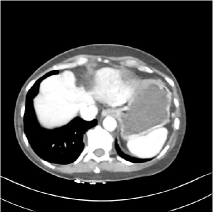

Refer to caption WavResNet [11]Refer to caption WavResNet [11]Refer to caption WavResNet [11]Refer to caption Momentum-Net (SimpleCNN)Refer to caption Momentum-Net (SimpleCNN)Refer to caption Momentum-Net (SimpleCNN)Refer to caption Momentum-Net (SimpleCNN-RSN)Refer to caption Momentum-Net (SimpleCNN-RSN)Refer to caption Momentum-Net (SimpleCNN-RSN)Refer to caption Momentum-Net (Dn-RSN)Refer to caption Momentum-Net (Dn-RSN)Refer to caption Momentum-Net (Dn-RSN)Refer to caption ReferenceRefer to caption ReferenceRefer to caption Reference

Fig. 3: Three examples (from top to bottom) of the reconstructed testing images using Momentum-Net with SimpleCNN (the second column), with SimpleCNN-RSN (the third column), and with Dn-RSN (the fourth column). The compared WavResNet denoised images are shown in the first column, and the reference images are in the fifth column. See their FBP images in Fig. 4.

Fig. 2 shows that the proposed Momentum-Net with SimpleCNN decreases RMSE dramatically in the first 30 layers, and tends to converge in 50 layers. The Momentum-Net reduces the mean RMSE value by 4.5 HU and gives smaller standard deviations in RMSE, compared to WavResNet, as reported in Table 1. This implies that the proposed Momentum-Net with SimpleCNN can improve both the accuracy and stability of low-dose CT image reconstruction than a state-of-the-art image denoising deep NN, WavResNet. The proposed Momentum-Net with SimpleCNN better removes noise and streak artifacts than WavResNet. It also provides clearer reconstructions of some details; see, in Fig. 3, the boundaries shown in the zoomed region at the top-right corner in the first example, the arrow pointed structures in zoomed areas of the second example, and the arrow pointed tissues in the left zoomed region in the third example.

We show the reconstructed examples by Momentum-Net with SimpleCNN-RSN and Dn-RSN in the third and fourth columns of Fig. 3 respectively. Comparing the first three and the last columns in Fig. 3, we observe that Momentum-Net with SimpleCNN-RSN provides generally noisier reconstructions than WavResNet and Momentum-Net with SimpleCNN. However, Momentum-Net with SimpleCNN-RSN sometimes can provide clearer details than WavResNet. For example, in the right zoomed box of the second example, Momentum-Net with SimpleCNN-RSN shows better reconstruction quality for the arrow pointed structures than WavResNet, and in the left zoomed box in the third row, the former gives clearer small tissues marked by red arrows than the latter. Table 1 reports that Momentum-Net with SimpleCNN-RSN is approximately 2.9 RMSE (HU) higher than WavResNet, while it has smaller standard deviations. This implies that Momentum-Net with SimpleCNN-RSN is more stable than WavResNet, although it may not provide better image qualities. Momentum-Net with Dn-RSN, however, provides the worst visual and numerical results among the compared four methods in this paper.